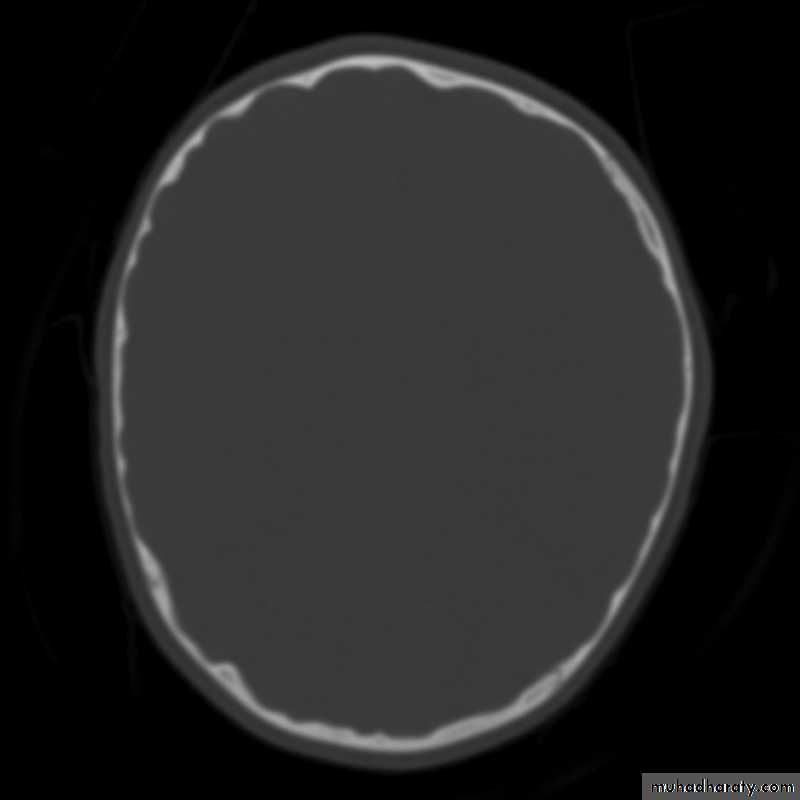

Skull X-ray findings in increased intracranial pressure

• Sutural separation in children.

• ‘Copper-beating’ marking of the cranial vault.

• Thinning of dorsum sellae.

• Erosion of the posterior clinoid process.

Copper-beating’ marking

Neuro surgery